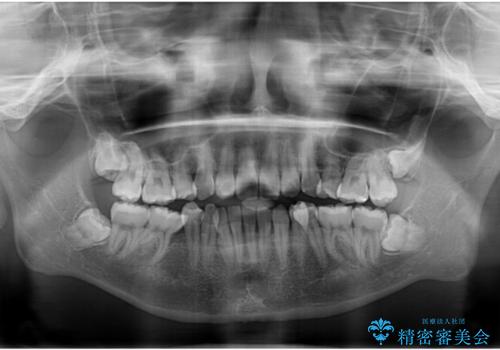

右側上下と左上の小臼歯が一本ずつ少なく、さらに骨格的な左右差もあり上下の真ん中の位置がずれています。

下顎のデコボコの解消と、真ん中の位置を改善するために左下の小臼歯を抜歯することとしました。

また、開咬を改善するため臼歯部にアンカースクリューを用いて圧下する力をかけていきました。